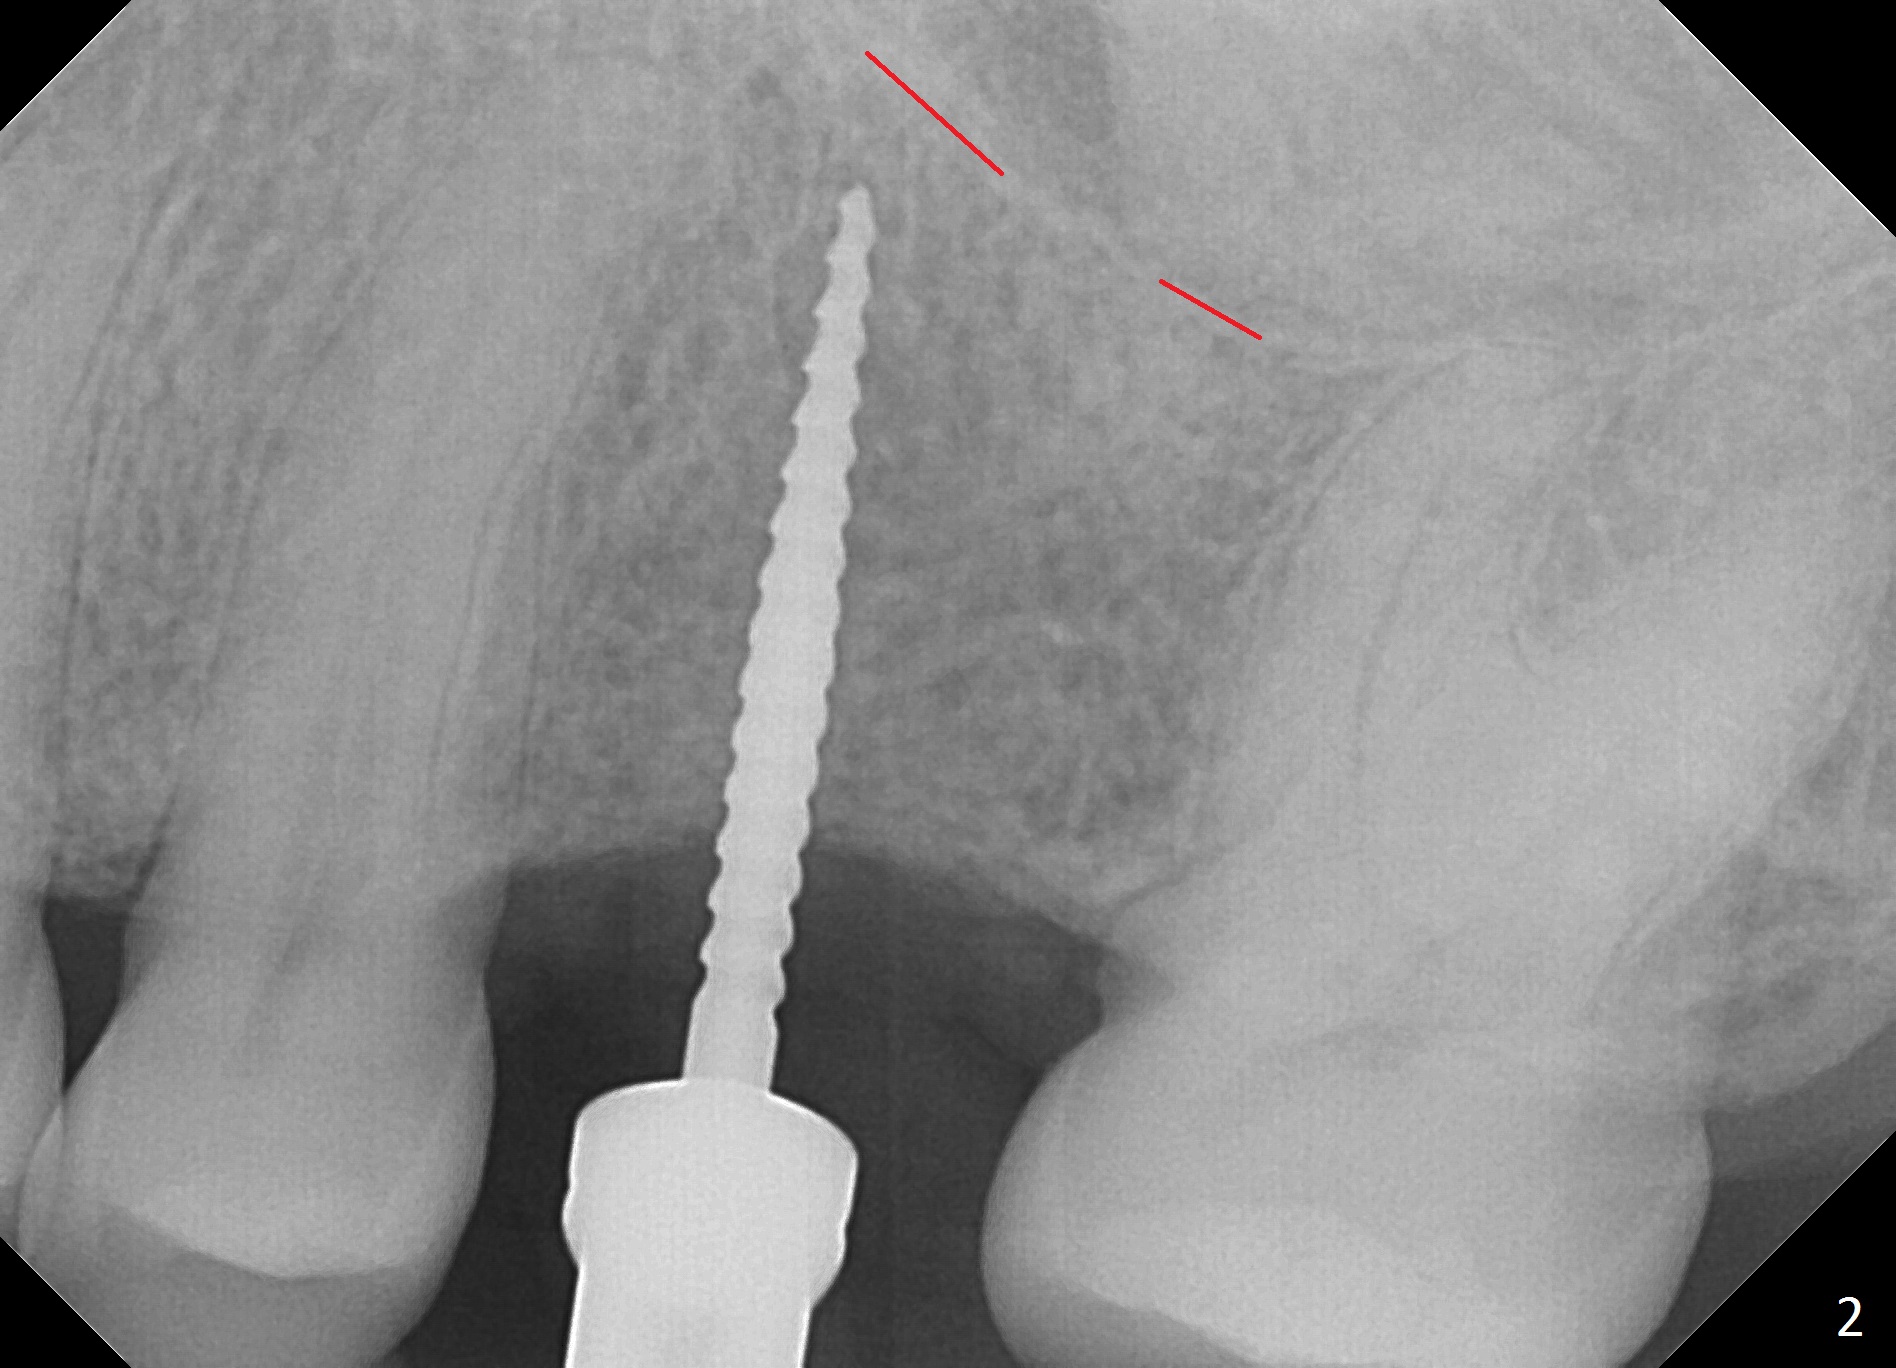

The edentulous area at #14 is moderately atrophic, After incision, the bone is too hard for #15 blade for bone expansion. Osteotomy is initiated with 1.2 mm drill, followed by insertion 1.3/2.3 mm bone expander (Fig.1). Use the same instruments are reused twice to change the trajectory (Fig.2,3). Finally Lindamann bur is utilized to move the osteotomy distally by ~ 2 mm; bone expansion continues until 2.4/3.7 mm expander for 13 mm with 50 Ncm (Fig.4). The last expander 3/4.4 mm barely enters the osteotomy for 6 mm. A 3.7 mm drill has to be used for 12 mm before placement of a 4.5x11.5 mm implant with >35 Ncm (Fig.5). A 5.5x5(3) mm abutment is placed with allograft (<) placed around the implant. Following suturing, periodontal dressing is applied around the implant. The abutment dislodges 3 months postop (Fig.6). Crown is delivered 3 weeks later. The abutment screw is retightened ~ 2 months later. He is a bruxer. The abutment screw is loose again <2 years post cementation (6 months post #18 screw retightenting and occlusal reduction), probably related to distal implant placement (Fig.7).